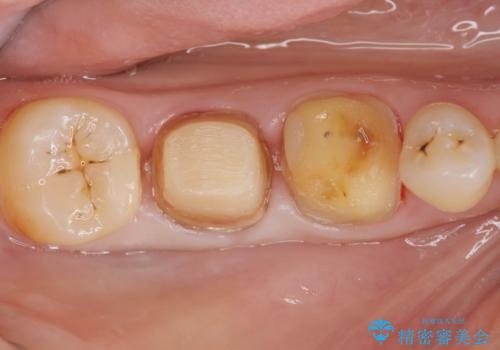

歯周ポケットの除去を併用したセラミック治療

適合や審美性に優れるセラミック治療を行う前に、歯周病の問題を歯周外科を行うことで解決し将来的に不安のないような口腔内環境を整備していきます。

治療前に4-5mm程度あった歯周ポケットは全て2mm以内となり、非常に清掃性が高く、歯周病の再発しずらい環境に整えた上でのセラミック治療を実践することができました。